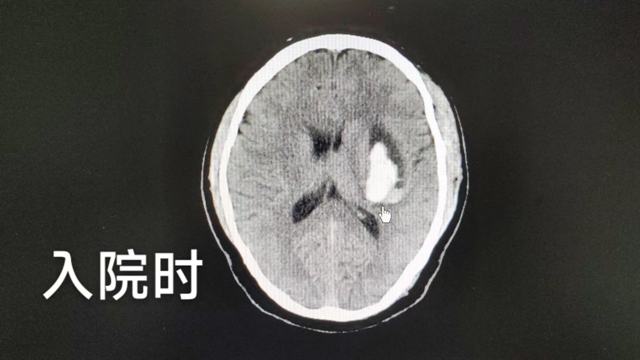

神经外科肖华医生接诊后,立即查看其颅脑 CT结果:左侧基底节区-侧脑室旁血肿,大小约3.8x1.8cm,左侧脑室受压变窄,中线结构稍右偏。

因患者起病时间短,意识昏睡、言语欠清,GCS评分9分,右侧肢体肌力2级,结合患者的职业特点和家属犹豫不决的情况,建议暂时对症治疗、观察、复查处理。

患者检查影像结果